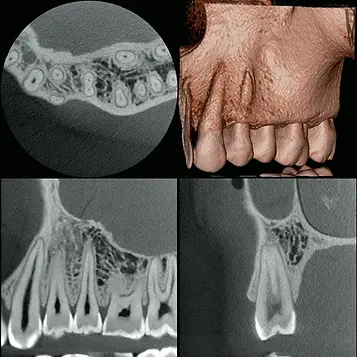

Cone Beam CT (CBCT)

We use advanced 3D cone beam imaging to evaluate teeth and surrounding structures with exceptional clarity. Unlike traditional two-dimensional X-rays, CBCT allows us to view teeth from multiple angles and assess complex anatomy with a high degree of accuracy. This technology supports more precise diagnoses and personalized treatment planning while maintaining a strong commitment to patient safety by using scans only when clinically necessary.